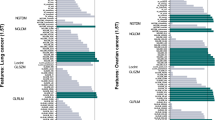

The heat maps in Figs. 3, 4, 5, 6, 7, and 8 show how the level of ICCmean varies with the entity of the translations in the two datasets. Figures 3, 4, and 5 show the ICCmean maps related to the OPC dataset using the three different histogram subdivisions, while Figs. 6, 7, and 8 show the ICCmean maps for the STS dataset. In Fig. 9a, examples of Diff%mean plot (with 95% confidence interval) for an unstable feature (signal quantile 0.1), a non-discriminative feature (short run emphasis), and a feature that is selected by the algorithm (signal mean) in the STS dataset can be seen. In Fig. 9b, the plot of ICCmean (with 95% confidence interval) for the same features can be seen. Since it is not possible to represent all the values of percentage variations and ICC, we refer to Tables 1–20 in the online resources, containing all the values of ICC10 and ICC100, together with the corresponding percentage variations.

Heat map of the mean ICCmean displayed according to features (rows) and entity of the translations (columns). The heat map refers to the oropharyngeal cancers (OPC) dataset and to the radiomic features computed with the 16-bin discretization. The features removed by the ICC-based feature selection technique are marked with an asterisk in the first column

Heat map of the mean ICCmean displayed according to features (rows) and entity of the translations (columns). The heat map refers to the oropharyngeal cancers (OPC) dataset and to the radiomic features computed with the 32-bin discretization. The features removed by the ICC-based feature selection technique are marked with an asterisk in the first column

Heat map of the mean ICCmean displayed according to features (rows) and entity of the translations (columns). The heat map refers to the oropharyngeal cancers (OPC) dataset and to the radiomic features computed with the 64-bin discretization. The features removed by the ICC-based feature selection technique are marked with an asterisk in the first column

Heat map of the mean ICCmean displayed according to features (rows) and entity of the translations (columns). The heat map refers to the soft tissue sarcoma (STS) dataset and to the radiomic features computed with the 16-bin discretization. The features removed by the ICC-based feature selection technique are marked with an asterisk in the first column

Heat map of the mean ICCmean displayed according to features (rows) and entity of the translations (columns). The heat map refers to the soft tissue sarcoma (STS) dataset and to the radiomic features computed with the 32-bin discretization. The features removed by the ICC-based feature selection technique are marked with an asterisk in the first column

Heat map of the mean ICCmean displayed according to features (rows) and entity of the translations (columns). The heat map refers to the soft tissue sarcoma (STS) dataset and to the radiomic features computed with the 64-bin discretization. The features removed by the ICC-based feature selection technique are marked with an asterisk in the first column